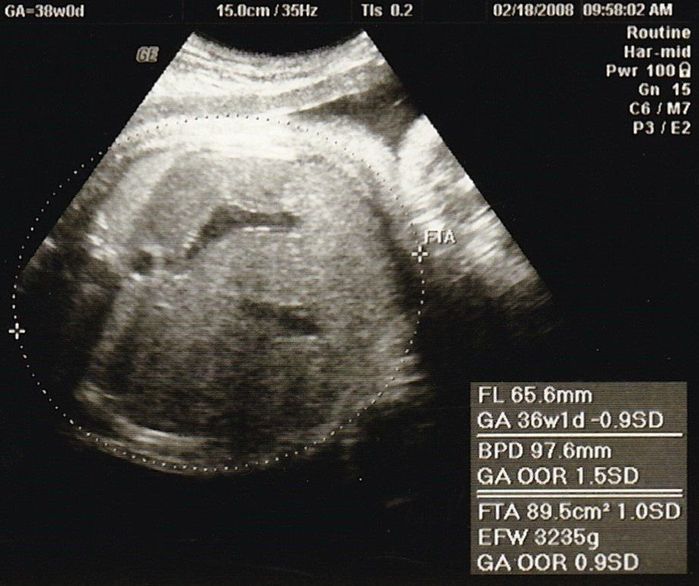

妊娠36週目のエコー写真

産院では、輸血が必要になったときのために、希望者は事前に自己採血し、院内保管してくれるということで、私は念のため希望しました。「たまごクラブ」や産院でもらった資料にある「入院準備のリスト」を見ながらチェックしました。